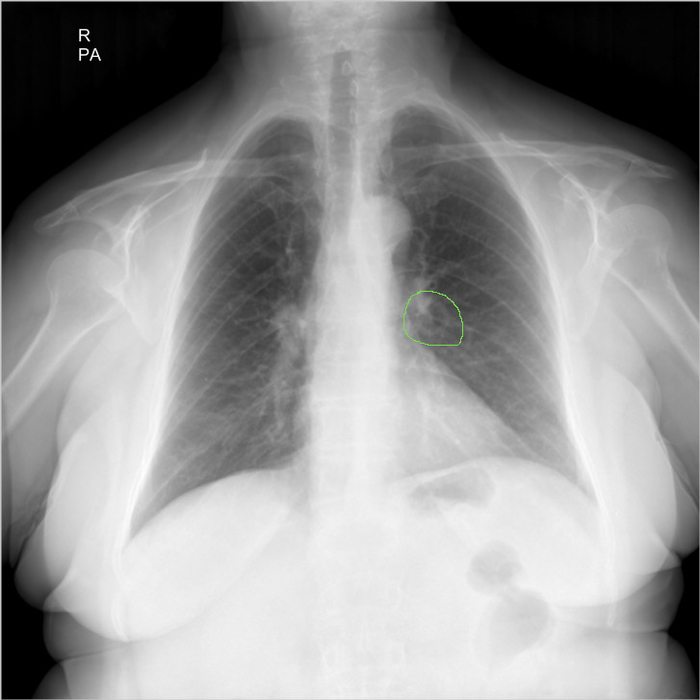

Здравствуйте, я работаю лаборантом в рентген кабинете, в госпитале, в Ливий. К сожалению у нас нет рентгенолога, и в некоторый случаях мне приходиться "читать" снимки самому... Со мной вместе работает мама, она медсестра в реанимаций. Ей сейчас 67 лет, решил сделать ей рентген лёгких, на боли в груди она не жалуется. Я начал изучать снимок и увидел образование в форме круга в левом легком возле бронха, подскажите мне пожалуйста что это такое и стоит ли мне беспокоится. Фото в негативе и позитиве прилагаю ниже.